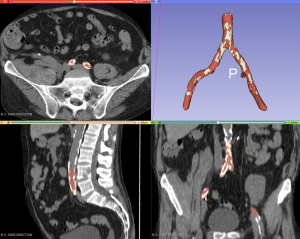

Every 3D-sliced module used for the study were natively included in the software, and we did not use an additional plugin. An inferior threshold was set at −20 Hounsfield units (HU) to model the aorta and the iliac vessels with the segment editor paint tool, while excluding perivascular fat. For calcified atheromatous plaques, the threshold was set at +300 HU. Residual artifacts were partially corrected by software, specifically the smoothing tool from the segment editor (median, opening, closing and joint smooth) (Figure 3). The working time required to obtain a printable file was 30 to 45 minutes. The printer created a hollow object from the solid object to reproduce the vascular wall with a thickness of 1.5 mm.